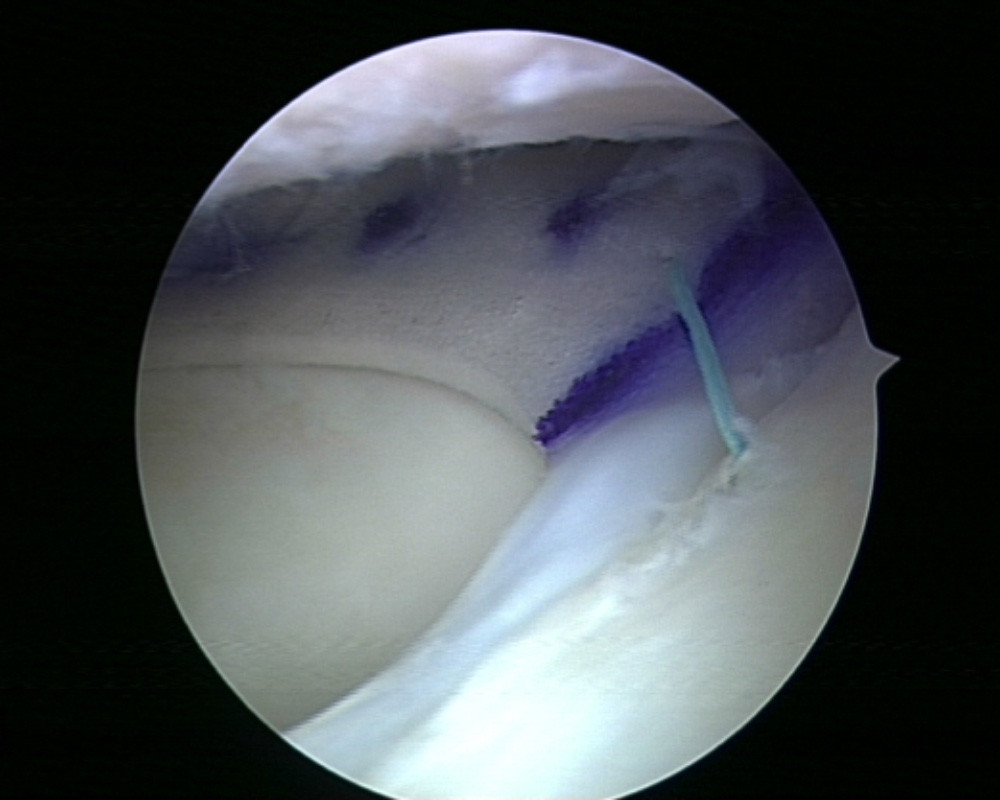

Insbesondere bei akuten Verletzungen des Meniskus kann dieser in vielen Fällen genäht und somit erhalten werden. Für die Erfolgsaussichten dieses Eingriffs ist eine frühzeitige Diagnose dieser Verletzung sowie eine zügige Einleitung der Therapie entscheidend. Die Operation selber erfolgt im Rahmen einer Gelenksspiegelung, sodass eine Eröffnung des Kniegelenkes vermieden werden kann. Für die Naht selbst stehen dem Operateur je nach Rissform und Lokalisation unterschiedliche Nahtinstrumente zur Verfügung. Nach der Operation ist in der Regel nach wenigen Tage eine Vollbelastung des Beines wieder möglich. Für etwa 6 Wochen wird die Beugung des Kniegelenk mittels einer beweglichen Schiene eingeschränkt um die Naht zu schützen. Maximalbelastungen des Kniegelenkes sollten für 3 Monate vermieden werden.

Meniskusnaht